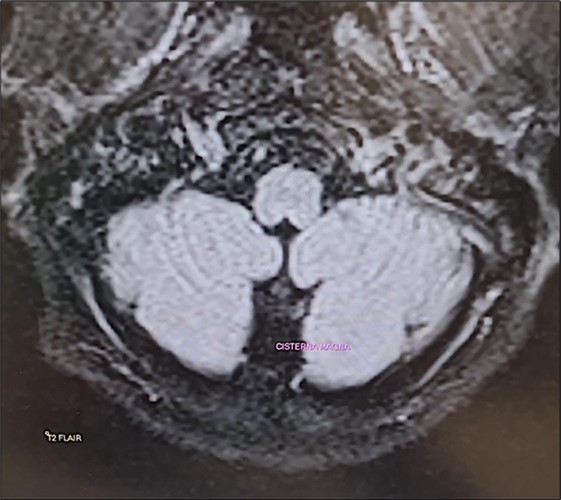

The Epley maneuver was performed with immediate effect (third evaluation; video 2). In fact, unsteadiness was reduced and gait was possible without assistance. Mild dysmetria remained in the finger-to-nose test. The intention tremor of the arms was almost completely resolved. Laboratory tests still showed hypomagnesemia (1.1 mg/dL) and hypocalcemia (7.5 mg/dL). Twenty-four-hour urinary magnesium was 9 mg (normal 73-122 mg). A new brain MRI confirmed the same findings as the previous one (Figure 1). Given the clinical improvement, intravenous magnesium sulfate supplementation was discontinued and daily oral magnesium citrate supplementation (1200 mg/d) was started. Cinnarizine-dimenhydrinate was discontinued, while the patient was advised to take l evosulpiride as needed. Follow-up was scheduled in 7 days or earlier if there was a change in clinical status.

Figure 1.Transverse section of brain MRI (T2 Flair) showing absence of cerebellar edema.

It is important to note that although the literature almost always reports MR-documented cerebellar edema18associated with hypomagnesemia, we did not observe the same finding in our patient in two consecutive brain MRIs performed approximately 15 days apart. It is possible that, although the authors do not specify the time at which this evaluation was performed in their patients, it was done at a stage in which hypomagnesemia had been present for some time. In our case, however, a very pronounced hypomagnesemia had developed hyperacutely, and perhaps the cerebellar edema described by other authors had not yet had a chance to develop. To the best of our knowledge, the case of a cerebellar syndrome induced by acute hypomagnesemia as a result of a benign and peripheral disease, has not been described.